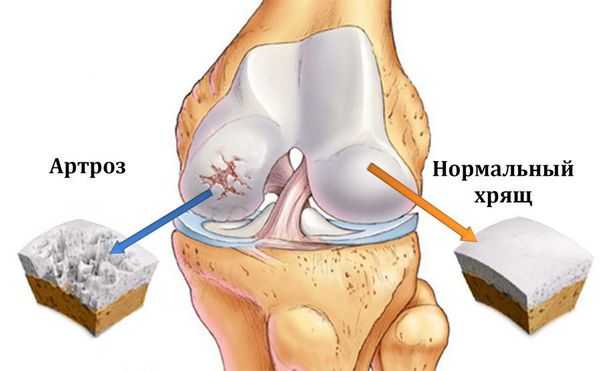

Артроз коленного сустава (гонартроз) — это прогрессирующее хроническое заболевание коленных суставов с повреждением, истончением и разрушением его хрящевой части (суставные поверхности бедренной и большеберцовой костей), а также поражением субхондральной кости. [2] [5] [16] Доказано исследованиями (артроскопия и МРТ), что помимо поражения суставного хряща в процесс вовлекаются мениски и синовиальная оболочка. Гонартроз — одна из самых распространенных ортопедических патологий. [4] [6] [9] [22] Существуют его синонимы — остеоартроз (ОА), деформирующий артроз. Заболевание является важной социально-экономической проблемой, так как широко распространено и значительно ухудшает качество жизни больных из-за постоянного болевого синдрома и, кроме того, становится причиной высокой инвалидизации. [15] [27]

До середины восьмидесятых годов прошлого века не было унифицированного определения заболевания. Только к 1995 году комитетом по остеоартрозу Американского колледжа ревматологии заболевание было охарактеризовано как результат действия механического и биологического факторов, приводящих к дисбалансу между процессами деградации и синтеза внеклеточного матрикса суставного хряща. [11] [19] В итоге происходит его разволокнение и дегенерация, образуются трещины, остеосклероз и уплотнение кортикального слоя субхондральной кости, растут остеофиты и формируются субхондральные кисты. [12] [29]

При артрозе (остеоартрозе) кроме прогрессивного разрушения хряща, потери его эластичности и амортизирующих свойств, в процесс постепенно вовлекаются кости. [7] [29] Под нагрузкой возникают заострения по краям (экзостозы), которые по ошибке считают "отложениями солей" — при классическом артрозе никакого отложения солей не происходит. Прогрессируя, артроз продолжает «съедать» хрящ. Затем деформируется кость, там происходит образование кист, поражаются все структуры сустава, и нога искривляется. [11] [17]

На второй стадии хрящевая прослойка резко истончается, а местами и вовсе отсутствует. [22] Появляются остеофиты по краям суставных поверхностей. Изменяются качественные и количественные характеристики синовиальной жидкости сустава — она становится гуще, более вязкой, что приводит к ухудшению питающих и смазывающих свойств. [14] [16] Боли более продолжительные и интенсивные, часто при движении появляется хруст. Отмечается незначительное или умеренное ограничение движений и небольшая деформация сустава. Прием анальгетиков помогает снять болевой синдром.

Отсутствие хряща на большинстве поражённых участков, выраженный склероз (уплотнение) кости, множество остеофитов и резкое сужение или отсутствие суставной щели. [8] [15] Боли практически постоянные, походка нарушена. Подвижность резко ограничена, заметна деформация сустава. Препараты НПВС, физиопроцедуры и другие стандартные методы лечения артроза коленного сустава неэффективны. [11]

Остеоартроз (артроз) — заболевание суставов, характеризующееся дегенеративным изменением покрывающего кость хряща, проще говоря, его разрушением.

Патогенез остеоартроза

Смазочная жидкость образуется в результате процесса ультрафильтрации сыворотки клетками синовиальной мембраны. Синовиоциты также вырабатывают гиалуроновую кислоту, гликозаминогликан. Синовиальная жидкость снабжает бессосудистый суставной хрящ питательными веществами, обеспечивает вязкость и эластичность, необходимые для поглощения ударов при движениях. В результате остеоартроза количество синовиальной жидкости уменьшается, суставные поверхности сближаются, в разволокнистом хряще обнаруживают эрозивные дефекты, которые прогрессируют до обнажения кости. Травмированная субхондральная кость также может подвергаться кистозной дегенерации, разрастанию остеофитов.